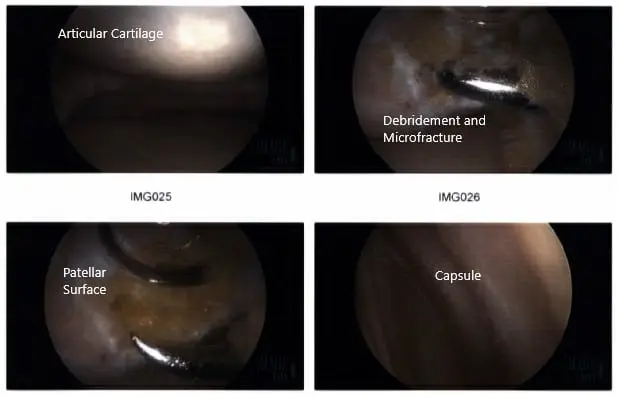

Intraoperative arthroscopic images.